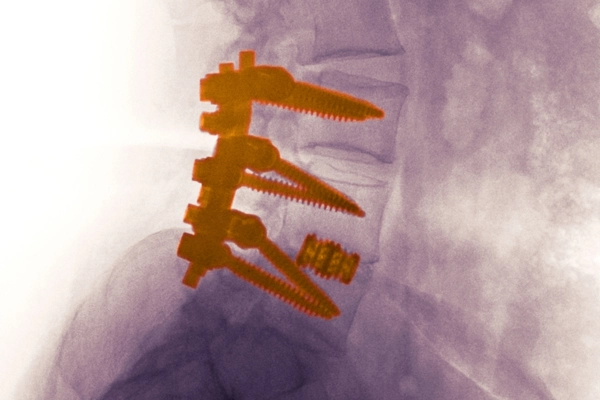

Para conseguir una buena soldadura se requiere que no haya movimiento, la ausencia de movimiento permite el crecimiento óseo lo cual se consigue mediante el uso de los famosos tornillos, barras y dispositivos intersomáticos (son cajas que se ponen entre las vértebras para aumentar la estabilidad y favorecer la fusión).

Fusiones vertebrales posteriores

Fusión vertebral posterolateral: En este tipo de artrodesis únicamente se busca que se fusionen las articulaciones facetarias. Es el tipo de fusión vertebral más sencilla.

Fusiones vertebrales 360º (PLIF Y TLIF): Se denominan fusiones 360º porque además de intentar que se fusionen las articulaciones facetarias también intentamos que se fusionen los cuerpos vertebrales. Para ello tenemos que quitar el disco lumbar e introducir una caja entre los cuerpos vertebrales que rellenamos de injerto. La ventaja de las fusiones 360º es que aumentamos el porcentaje de éxito de la cirugía ya que la caja intersomática aumenta el área de fusión y da más estabilidad al montaje.